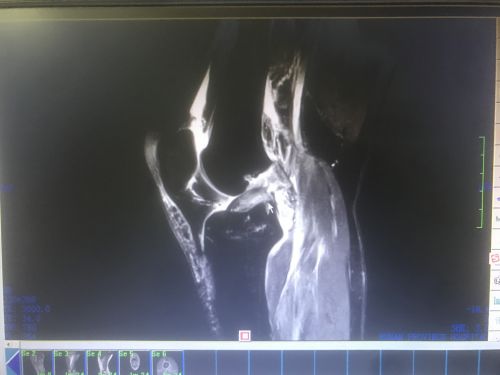

术前MRI显示:前交叉韧带完全断裂(鼠标所示)。

入院完善磁共振等检查,证实了之前的判断。由于韧带断裂无法自愈,只能通过手术修补。王靖主任医师组织医护人员商讨病情,制定周密的手术方案后,带领团队为患者施行关节镜下右膝前交叉韧带重建术。由于断裂的韧带失去修复功能,只得取大腿内侧韧带“移植”到受伤的右膝上;术中发现右膝半月板也有损伤,医生一并进行了缝合。手术历时2小时顺利完成,术后当天,唐女士就在医生指导下进行直腿抬高和扶拐行走训练,并于手术3天后出院。